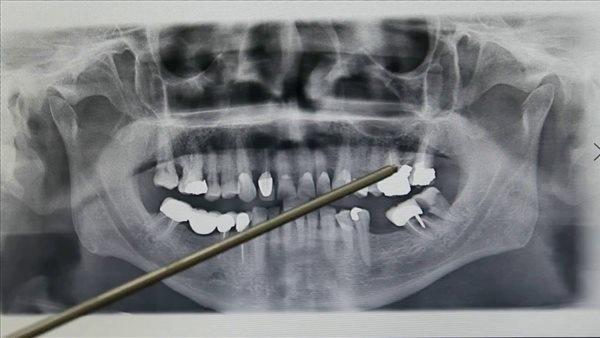

وكشفت نتائج دراسة جديدة، أن الأشعة السينية للأسنان قد تسبب الإصابة بالسرطان أو مرض التهاب السحايا، إذ أثارت مخاوف بشأن ضرورتها وسلامتها نتيجة الإفراط في استخدامها والمخاطر الصحية المحتملة والتكاليف المالية.

وتجرى الأشعة السينية للأسنان عن طريق إصدار دفعة محكومة من الإشعاع، والتي تمر عبر الفك والأسنان لإنشاء صور مفصلة لهياكلها الداخلية، ومع ذلك، فإن التعرض للإشعاع من الأشعة السينية للأسنان يُعد ضئيل.